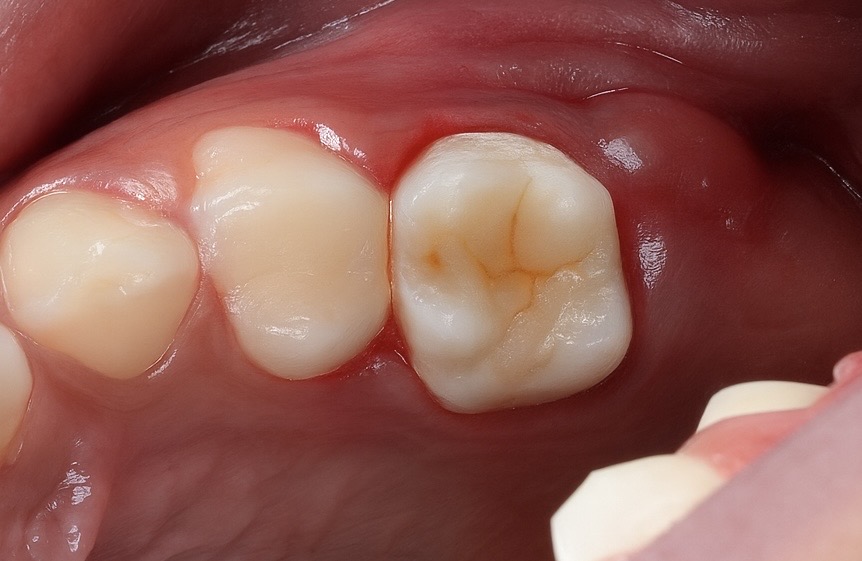

Rubber-dam isolation achieved to prevent contamination (Fig 2). Conservative access prepared under magnification. Coronal pulp tissue removed, and canal orifices located using DG-16 explorer.

- Fig 2: Rubber-dam isolation and conservative access.